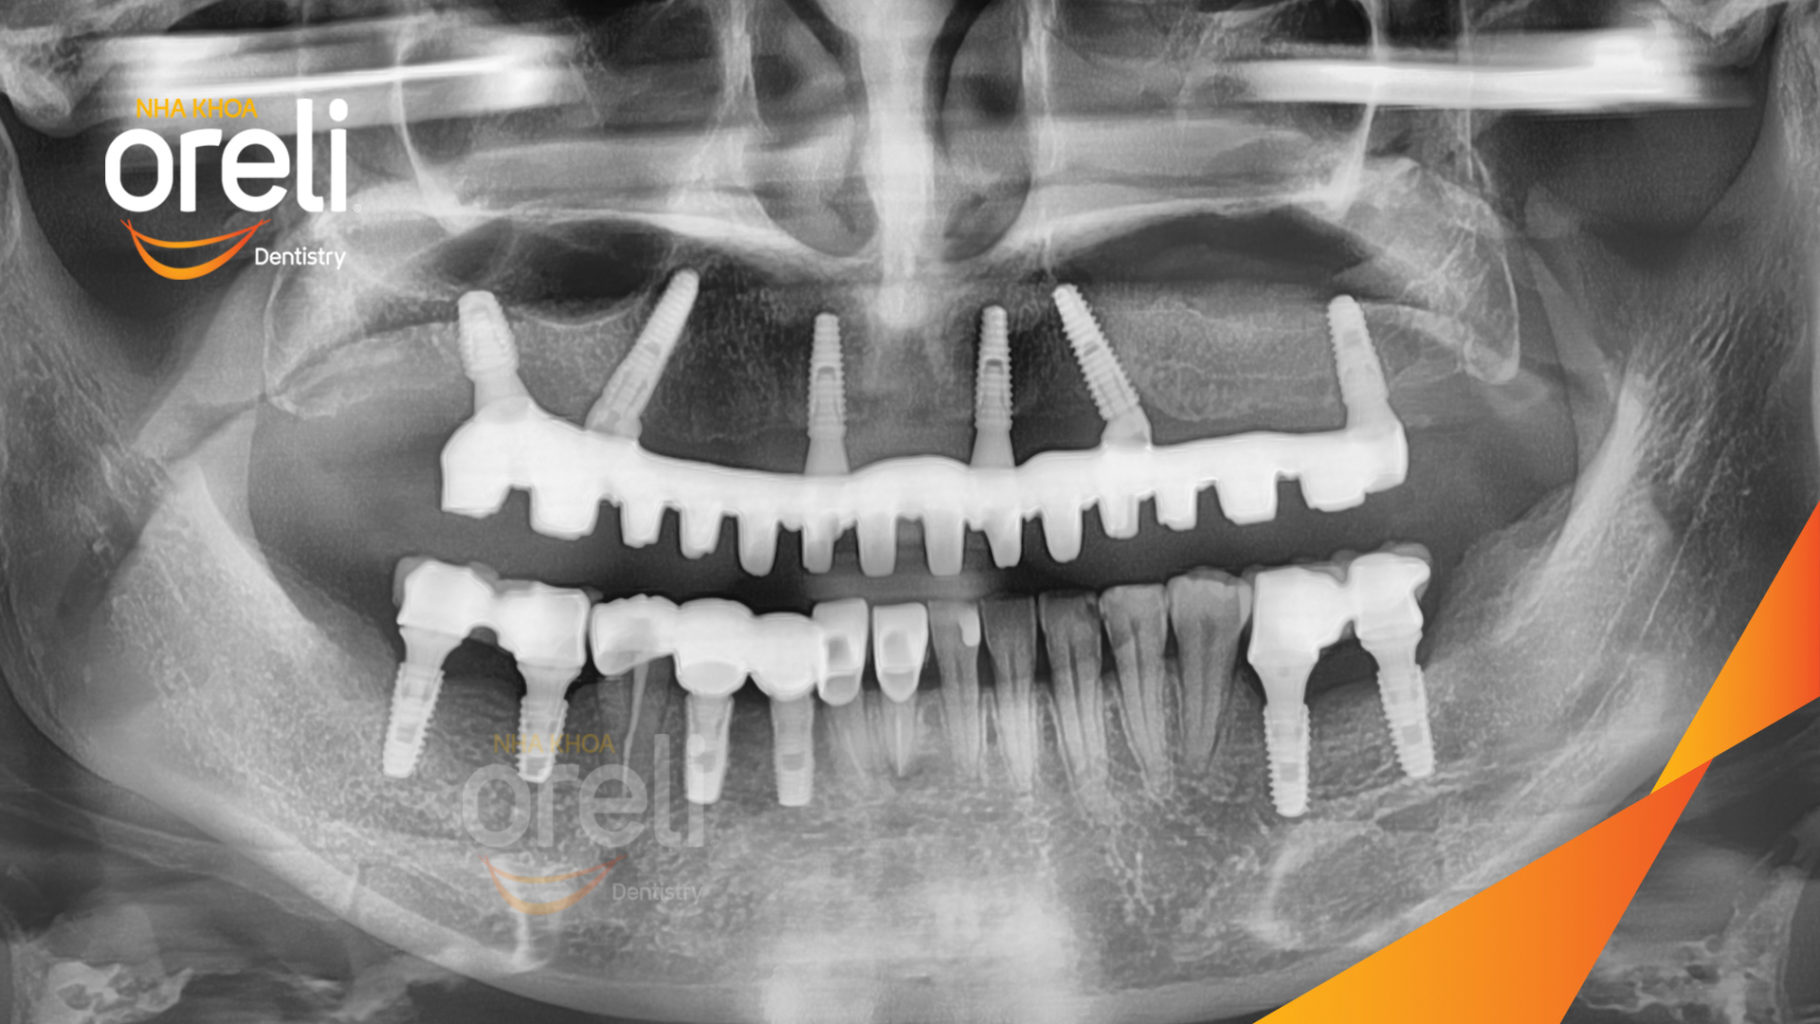

Ca cấy ghép Implant toàn hàm trên và 6 răng implant đơn lẻ hàm dưới tại Oreli

Ca trồng răng implant toàn hàm phục hồi ăn nhai và thẩm mỹ nụ cười. Kết quả thực tế trước và sau điều trị tại Nha khoa Oreli.

Hình ảnh thực tế